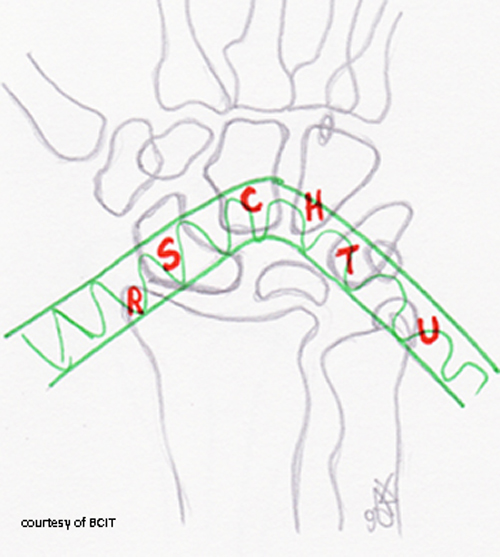

Where do most carpal bone fractures/dislocations occur?

In the vulnerable zone/arch of the wrist — ulnar side gets more severe injuries.

Why is wrist positioning critical in trauma imaging?

To prevent misinterpretation and to align radius, lunate, capitate, and 3rd metacarpal for accurate diagnosis.

What radiographic sign is used to confirm proper carpal alignment?

The alignment of the third metacarpal, capitate, lunate, and radius on a lateral view (the “teacup” effect).